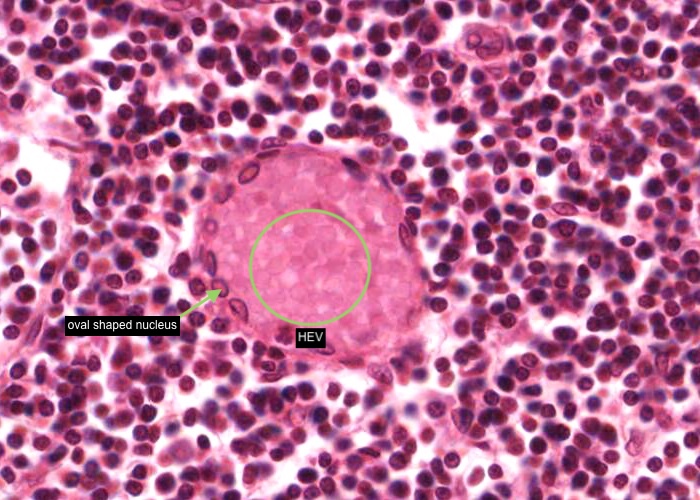

The important specializations of this vasculature are the tall postcapillary venules (TPCV), also called high endothelial venules (HEV). These vessels are lined by specialized cuboidal epithelium, look for an oval shaped nucleus (sometimes even described as columnar) instead of the usual squamous variety. They are located in the paracortex as the first segments of the venules.

Recall their role in the pathway of lymphocyte circulation. See if you can find several examples and even some sectioned transversely (see next item). If not, you will have no problem recognizing them if you go back and re-examine the section of the tonsil.

In this image, the tall postcapillary venule (TPCV), also called a high endothelial venule (HEV), is sectioned transversely. Look for an oval shaped nucleus (sometimes even described as columnar) instead of the usual squamous variety.

Some lymphocytes live for a very long time and so recirculate continuously. Their "homing behaviour" is a consequence of molecules on their cell surface interacting with complementary molecules on the endothelial cell surface of these specialised venules.